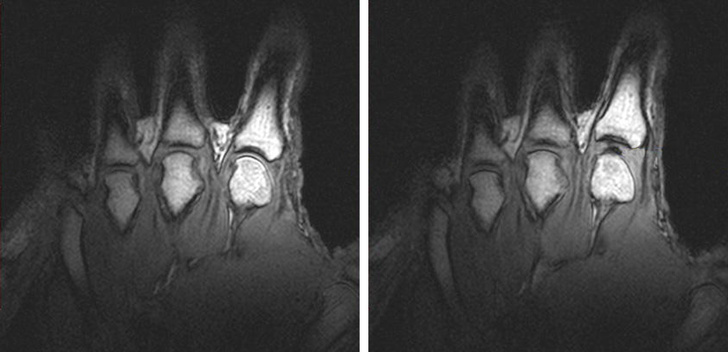

Темна пляма між суглобами праворуч — порожнеча, яка утворюється під час хрускоту.

Багато вчених сходяться на думці, що звук, який з'являється при хрусте пальцями, виникає з-за лопаються бульбашок в синовіальній рідини, що знаходиться між суглобами. Але вони досі не можуть точно пояснити, чому цей хрускіт настільки гучний.

Рідина, яка знаходиться між суглобами, містить кисень, азот і вуглекислий газ. Коли ми розтягуємо суглоби, газ звільняється і з'являються бульбашки, які лопаються. Щоб знову хрустнуть тим же пальцем, необхідно почекати, поки гази рідини не накопичаться знову.

Одне дослідження, в якому було змодельовано процес хрускоту, показує, що гучний звук тільки частково виходить від лопаються бульбашок. Звідки береться інша частина звуку, незрозуміло. Якщо це не суглоб, не бульбашки, то що це може бути?